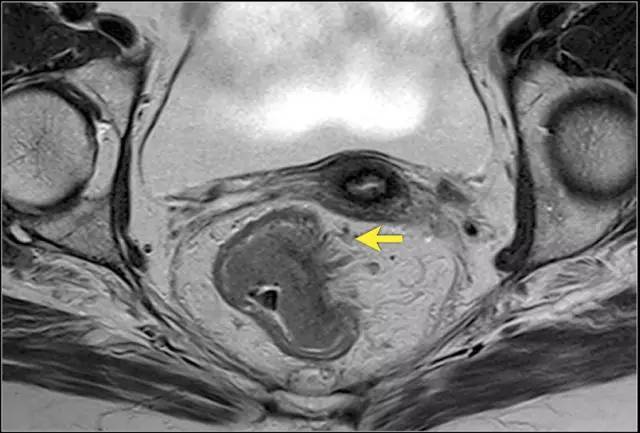

图 14 轴向 T2 加权图像上,沿着内脏腹膜有肿瘤向内生长(箭头)

低直肠完全被直肠内筋膜覆盖。在直肠中部,其后侧和外侧由直肠内筋膜覆盖,但在前侧由内脏腹膜覆盖。内脏腹膜生长意味着扩散到腹膜腔。在矢状 T2 加权图像上,腹膜反折可以描绘为连接膀胱与直肠前后方面的低信号细线。

T4a 分期,侵出腹膜反折